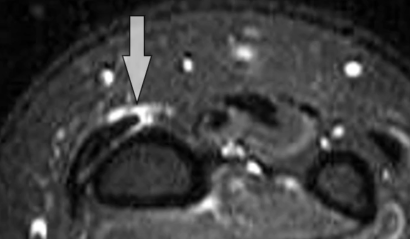

Syndrome de l’Intersection Distale

- Croisement des 2e et 3e compartiment (Extenseurs du Carpe Vs Long Extenseur du Pouce)

- Se fait 4cm plus bas que le tubercule de Lister (bien couvrir sur IRM !)

- Oedème Péritendineux (pas dans la gaine)